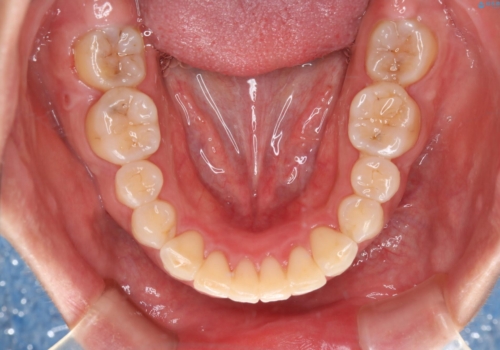

- 審美装置(ワイヤー)

- 前歯のがたつきが気になるとご相談にいらした方です。当初は前歯の部分矯正をご希望されていましたが、全体的に整えることで審美的、機能的な歯並びとなりました。

当初は上顎前歯のみの部分矯正をご希望されていましたが、部分的に前歯のみを並べると出っ歯感がつよくなり、食事もしづらくなる可能性をお伝えしました。全顎的な矯正治療により、審美的、機能的な歯並びとなりました。